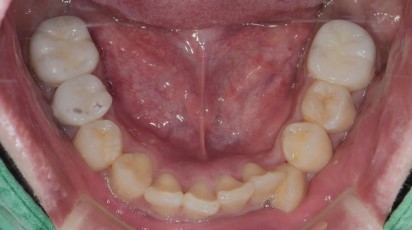

治療後 :套上假牙套+無牙根缺牙處靠牙橋復型,洗牙減緩牙齦發炎

牙根穩固了,牙周健康了,猶如樹根穩穩地抓住肥沃土壤,樹木自然能成長茁壯!!! 套上牙套調整咬合,恭喜您畢業了!!!!

假牙復型